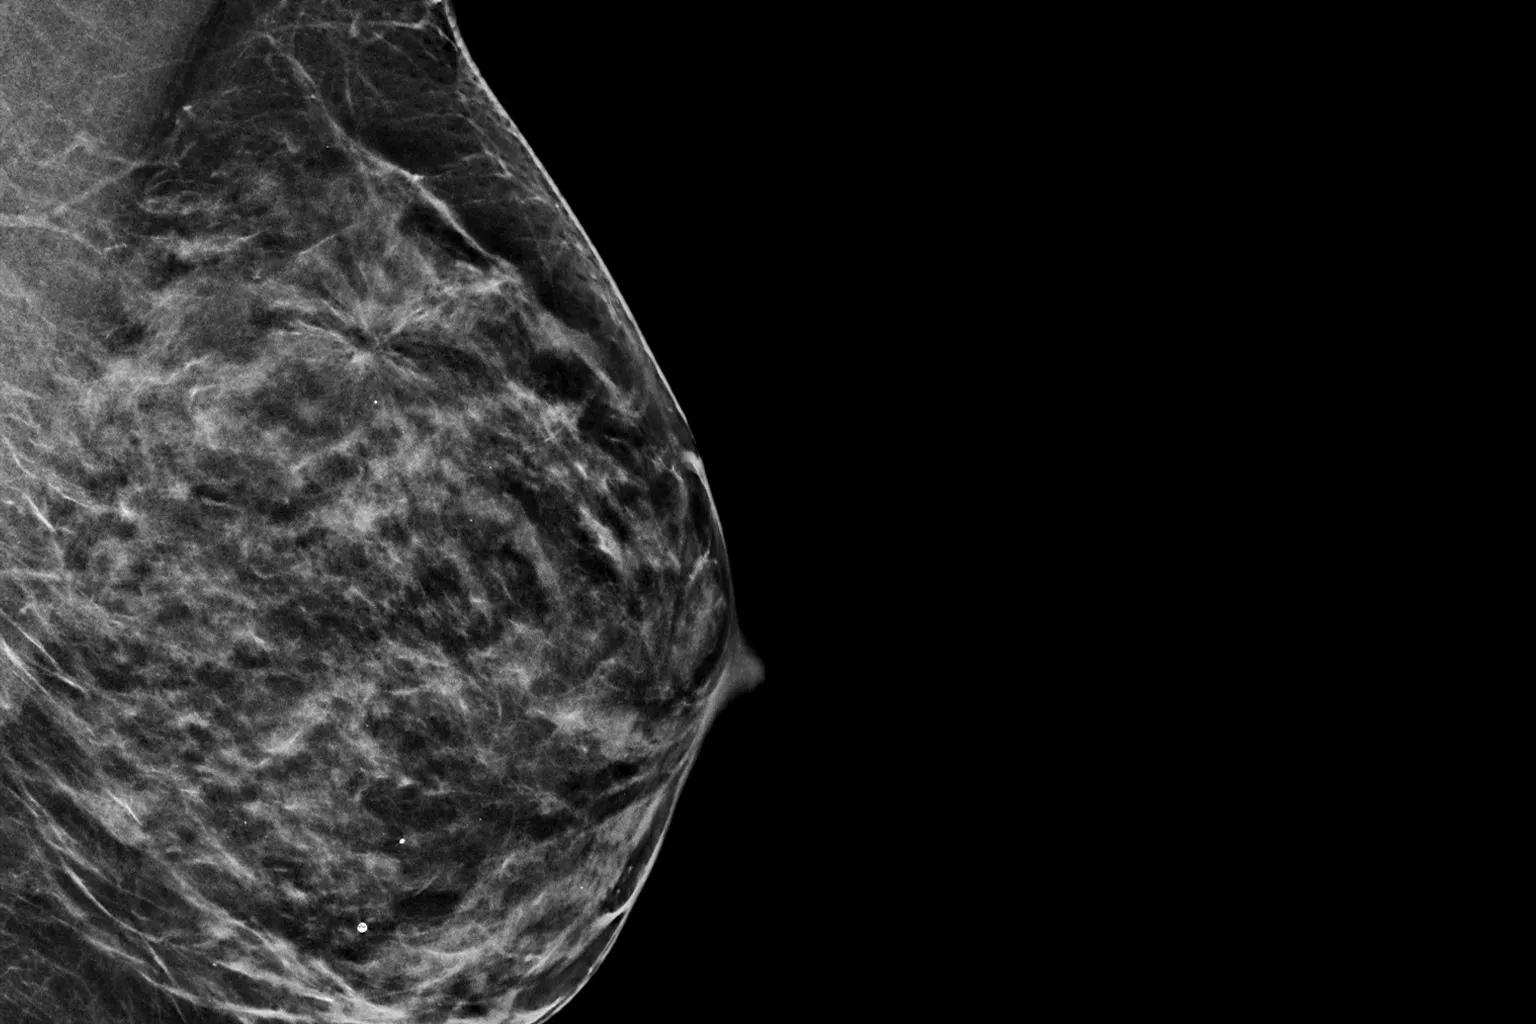

C-View 2D 画像では、微小石灰化でよく見られる構造の歪み、腫瘤性病変、および輝点が、従来の FFDM 2D 画像や断層スライスよりもよく見えます4,6-9

C-View 2D 画像では、微小石灰化や構築の乱れ、腫瘤性病変、および輝点が、従来の FFDM 2D 画像や断層スライスよりもよく見えます4,6-9